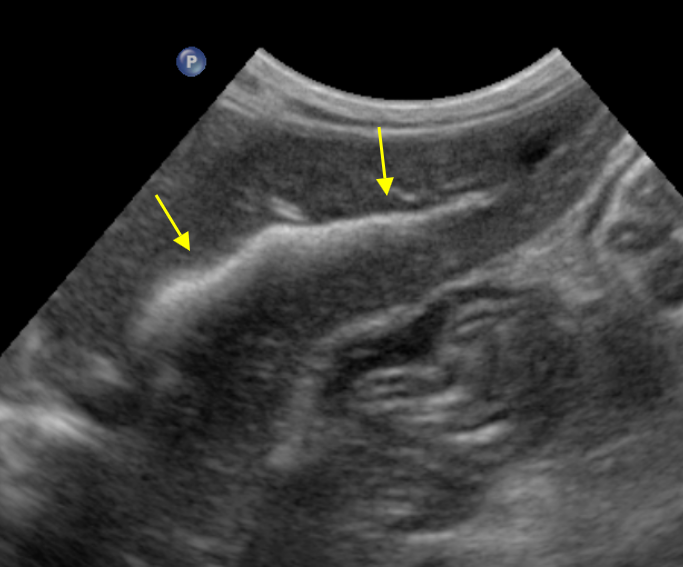

feline intrahepatic bile calculi : radiography

ultrasonography

branched intrahepatic bile duct stone